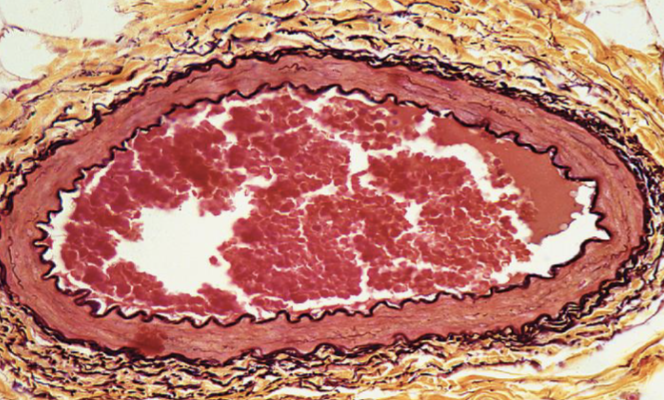

Identifique tipo de tejido conectivo

elastico

Indique sitio anatómico dónde se encuentra

vasos sanguineos